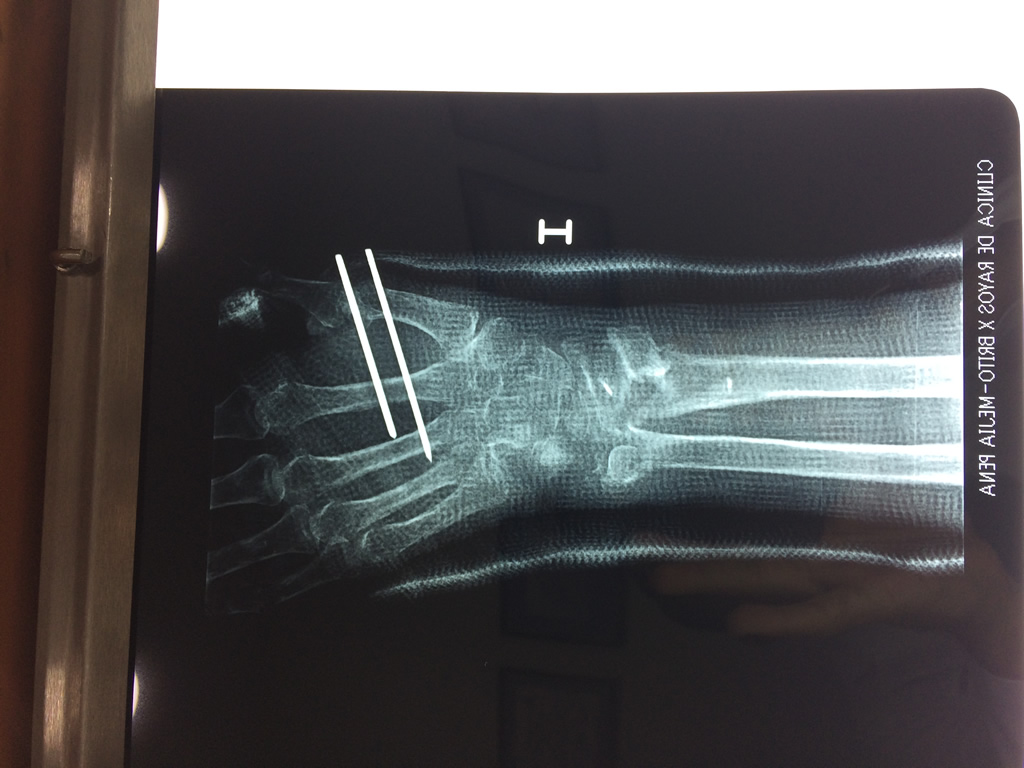

Cirugías de Codo - Cirugías de Muñecas y Manos

Los procedimientos más comunes en cirugía de la mano son aquellos destinados a reparar traumatismos, incluyendo lesiones de tendones, nervios, vasos sanguíneos, y articulaciones; huesos fracturados; y quemaduras, cortes, y otros daños de la piel.